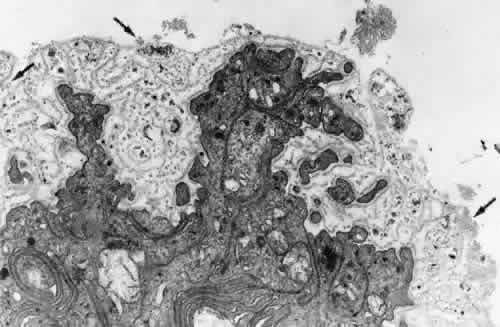

By light microscopy, zonular fiber bundles are eosinophilic, PAS-positive structures, often appearing to be ribbons connected by a paler interbundle “membrane” (Fig. 6). By scanning electron microscopy, the ribbons appear as groups of striated fiber bundles held together by a loose fibrogranular meshwork. Each fiber is composed of fibrils 10 nm in diameter, highly oriented and closely aggregated. Ultrastructurally, these fibrils have a tubular profile in cross section and a microperiodicity of 12 to14 nm seen along the fibril (Fig. 7). Dyes that precipitate and bind to polysaccharides show irregular granules and rod-like associated material on and between the fibrils.

Fig. 6. By scanning electron microscopy the ribbons of fiber bundles appear striated (× 2,200). Inset A. The flat ribbons of zonular bundles have a paler-staining “membrane” holding them together (arrow) (H&E, × 220). Inset B. The fibers are composed of highly oriented and tightly aggregated fibrils (× 23,000).

Fig. 7. Zonular fibrils average 10 nm in diameter. Most show a microperi-odicity of 12 nm (arrow) and they frequently appear hollow in cross section (small arrows). (TEM, × 81,600) Inset. C is lens capsule. The dark dots and filaments adherent to each zonular fibril are polysaccharide components preserved by fixatives containing Alcian blue (TEM, × 100,000).